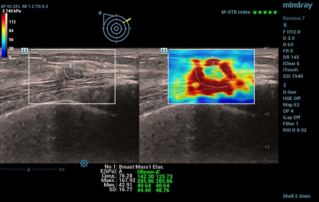

Female pelvic floor anatomy, which developed since the early 20th century, has had a variety of theories, including integral theory, three levels of vaginal support theory, "hammock hypothesis", and three-chamber system. Supporting structures such as pelvic floor muscles, fascia and ligament play an important role in maintaining the normal function of pelvic floor, among which levator ani muscle group is one of the most important supporting structures.